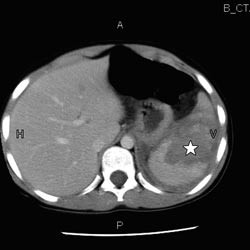

Av de resterende 11 pasientene var ni gutter og to piker. Hyppigste skademekanisme var fall (seks tilfeller), mens sykkelvelt og akeulykker var årsak i to tilfeller hver. Median alder ved innleggelse var åtte år (spredning 1 – 12). Median skadegrad av milt bedømt ved CT var 4 (spredning 3 – 4) (fig 1). En 12 år gammel pike ble hemodynamisk ustabil kort tid etter innkomst. Hun fikk transfusjonsbehandling, men var fortsatt ustabil og gjennomgikk deretter vellykket intervensjonsradiologisk embolisering av miltarterien. De øvrige pasientene var hemodynamisk stabile etter innleggelse. Median liggetid i sykehuset var fem døgn (spredning 3 – 8), hvorav null døgn (spredning 0 – 4) i overvåkningsavdeling. Mediant antall ultralydkontroller som ble utført i etterforløpet av miltskadene, var to (spredning 0 – 4). Resultatet av disse kontrollene viste begynnende eller fullstendig normalisering av milten. Anbefalt redusert aktivitetstid etter skaden var mediant fire uker (spredning 3 – 6), frem til en poliklinisk avsluttende kontroll. Det ble ikke registrert senblødninger eller andre komplikasjoner hos noen av pasientene.

CT vil ofte være den foretrukne modalitet ved primærutredning av stumpt abdominaltraume hos barn. På grunn av strålebelastningen CT-undersøkelsen representerer, bør indikasjonsstillingen være god. Skader av milten bedømmes internasjonalt ved vurdering av CT-bilder og graderes etter stigende alvorlighetsgrad etter den såkalte organ injury scale (6). Hemodynamisk stabile barn med isolert miltskade kan behandles ikke-operativt uavhengig av skadegrad bedømt radiologisk (1) – (4). I vårt materiale hadde vi kun alvorlige skader (grad 3 og 4) (fig 1), men ikke-operativ behandling lot seg likevel gjennomføre hos alle pasienter.